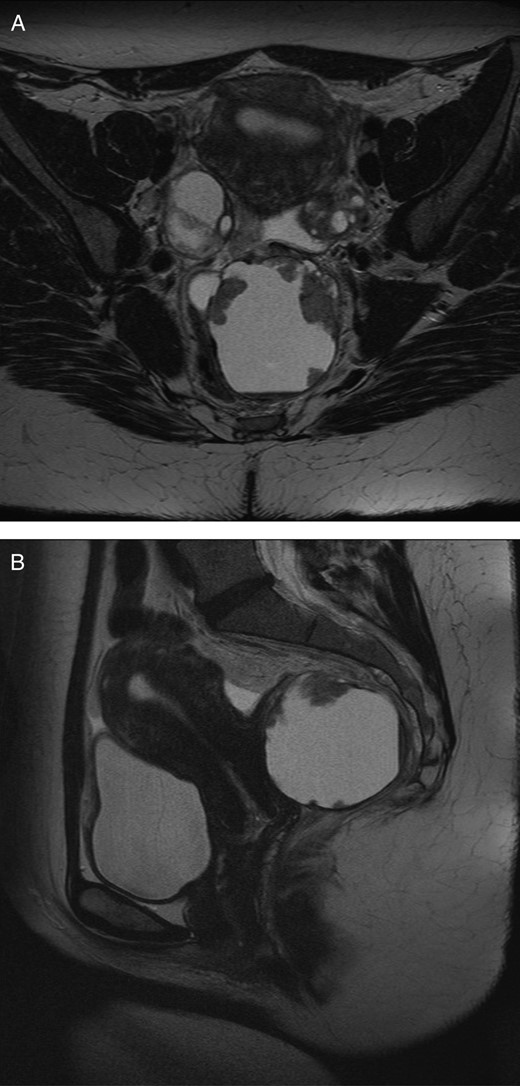

A 35-year-old woman attended as an emergency admission with lower abdominal pain. Her clinical and haemodynamic parameters were in keeping with acute appendicitis, and a diagnostic laparoscopy was undertaken that identified an adenexal mass. A subsequent computed tomography (CT) and magnetic resonance imaging (MRI) of her abdomen and pelvis demonstrated a mass arising in the right retrorectal space comprising of complex papillary nodules, breaching the capsule in which it was contained. The lesion filled the entire mesorectal envelope and was in contact with the vagina and left levator plate (Fig. 1A and B). Both MR and CT appearances were in keeping with malignant change in a retrorectal duplication cyst (TGC) with extra-capsular spread.

(A) Axial MRI image of pelvis demonstrating retrorectal cyst. (B) Sagittal MRI image of pelvis demonstrating retrorectal cyst.